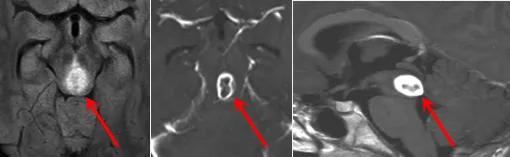

术后影像

几天后,手术如期进行,并在巴教授团队数小时奋战下取得成功,肿瘤被顺利切除。病理显示为WHOⅢ级间变性星形细胞瘤(Anaplastic Astrocytoma)。

如今,在巴教授15年的随访下,马修已经顺利成年,尽管他的童年遭遇过不幸,但一场成功的手术,为他争取到了完整的少年与青年。看着如今笑容满面、意气风发的马修,父母无比庆幸当年的选择没有给孩子造成严重的后果,反而挽救了他。